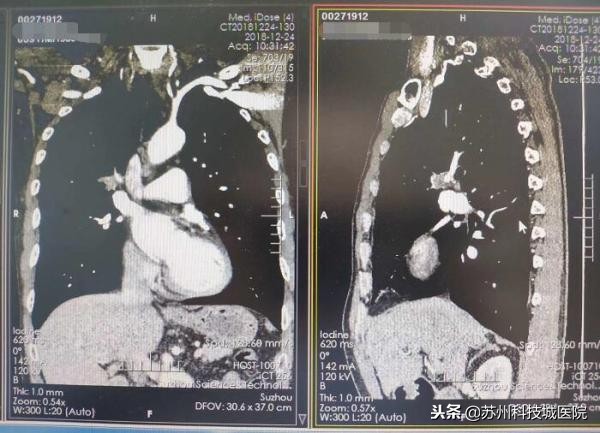

今年59岁的张大伯是一个有着近三十年吸烟史的“老烟枪”,12月下旬,觉得胸口难受的他在儿子的陪同下来到了苏州科技城医院心胸外科,在一系列问诊、CT检查后,心胸外科主任谢骏凭借着丰富的临床经验,明确张大伯得的是右上前段开口鳞癌,且为非常复杂的中央型肺癌中晚期。他第一时间将诊断结果及利害关系告知了张老伯父子,并建议张老伯立即住院,准备手术。张老伯有些犹豫,他希望等病理结果出来再做决定。

要知道,中央型肺癌因为肿瘤位置靠近肺门且隐蔽,周边大血管多,发展到中晚期后,肿瘤细胞将随血流全身扩散,同时还会随着淋巴结转移。如果不及时手术治疗,短时间内可能会出现远处转移,到时候就失去了手术机会。而中晚期的中央型肿瘤,如果不进行手术,患者的3年存活率小于30%,5年存活率更是低于5%。张大伯的手术,可谓刻不容缓!

谢主任介绍,事实上,针对中央型肿瘤患者,因为肿瘤大、手术风险大、难度大等原因,仅有20%左右的患者有条件接受手术治疗。幸运的是,张大伯具备手术条件。考虑到张大伯的肿瘤位置太靠近中央,包绕了肺动脉等重要血管,而且肿瘤已经侵犯到血管和气管,常规的手术入路非常容易损伤肺动脉,引起大出血而导致患者死亡,风险太大。而开胸手术的恢复期大约在一个半月左右,显然太长。经过综合考量,谢主任为张大伯“量身定制”了一个特别的手术路径——单孔手术,先切断支气管,再处理受侵犯的血管,通过微创手术的形式,远离肿瘤进行切除。为了确保术后没有残留一个癌细胞,在术中,谢主任还为张大伯做了冰冻病理,以及系统淋巴清扫。